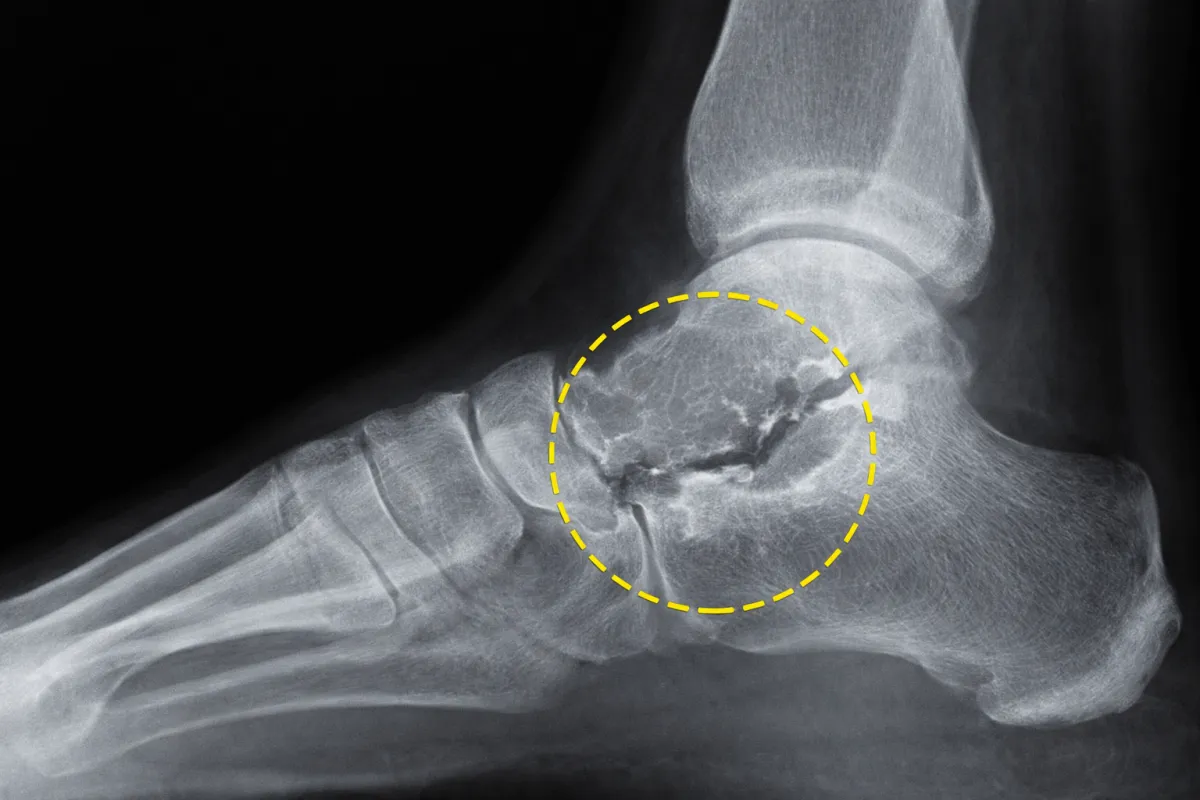

Radiografia

Riduzione dello spazio articolare

Osteofiti